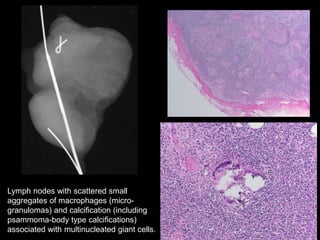

Lymph nodes with scattered small

aggregates of macrophages (micro-

granulomas) and calcification (including

psammoma-body type calcifications)

associated with multinucleated giant cells.

LN โ€œCalcificationsโ€